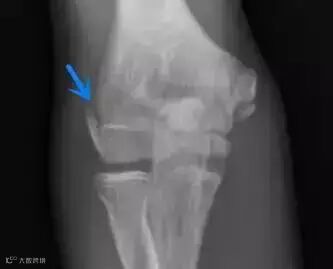

平片:肱骨内上髁骨骺板增宽、分离,但无撕脱。

3.病史和体格检查对诊断很关键,损伤的时间和机理,疼痛的部位、症状为诊断的关键因素。平片上肱骨内上髁炎表现为一系列征象:肱骨内上髁透亮线、分离或硬化,骨骺板增宽。MRI肱骨内上髁可见长T1长T2信号影,骨骺板增宽,有时同时可见屈肌总腱的T2信号增高。